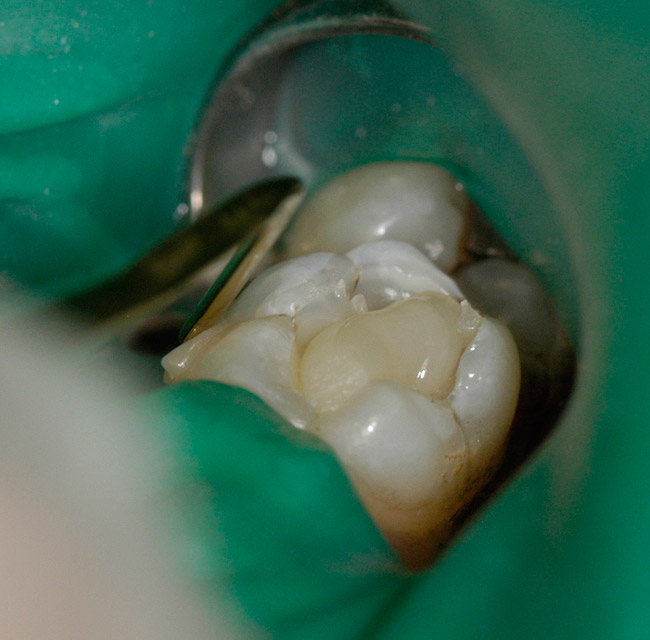

Figure 4   Adhesive is applied and gently air-dried and light-cured per the manufacturer’s suggestion. The cavity is then filled with the dentin replacement composite, shade A-3, and shaped like the dentin underlying the cusps of the tooth. This composite is then light-cured.

Figure 4